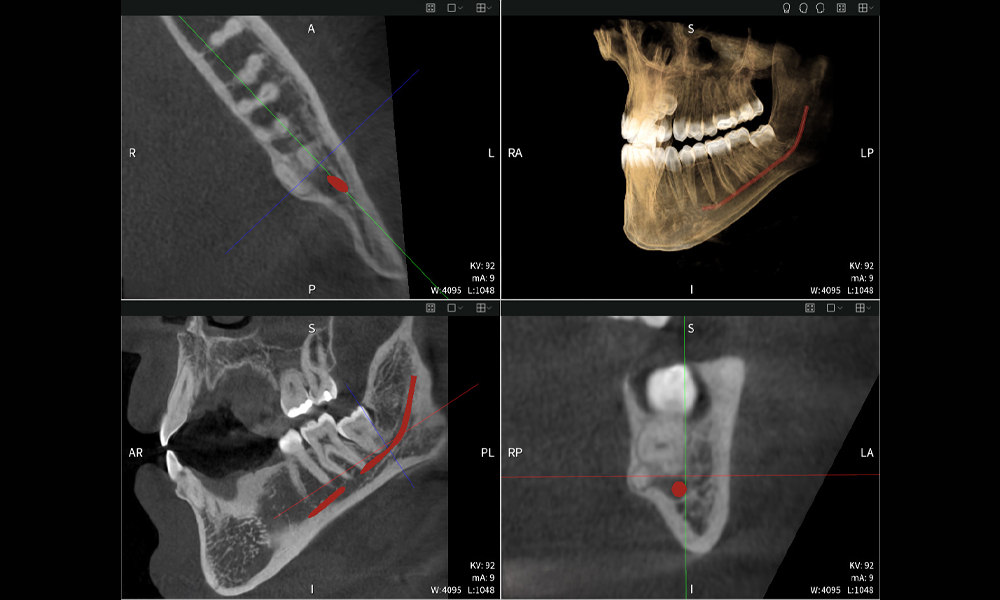

Figura d: Resultados de imagen de Seethrough Max, sobre un fondo negro.

Figura d

Las figuras b–d muestran varias vistas de una reconstrucción 3D de la mandíbula, proporcionando una visión general completa de la anatomía mandibular, la posición de los nervios en relación con los dientes y permitiendo evaluar la simetría y alineación dentaria.

La figura d muestra el diente 48 previamente tratado, con la corona retirada y las raíces dejadas en proximidad al nervio, lo que ilustra el alto riesgo de daño nervioso.